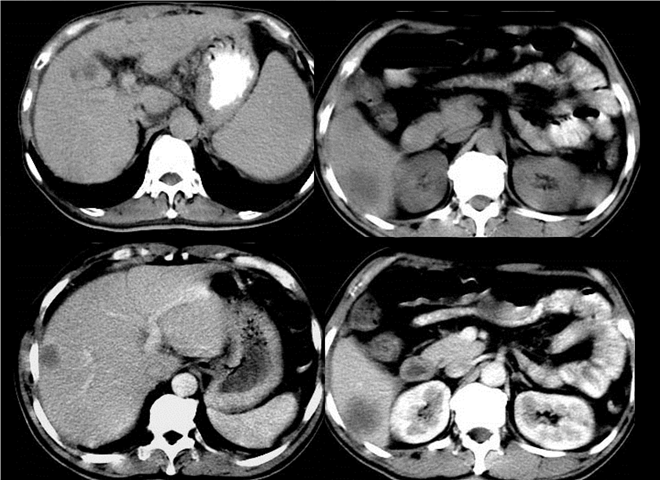

13_CT增强扫描